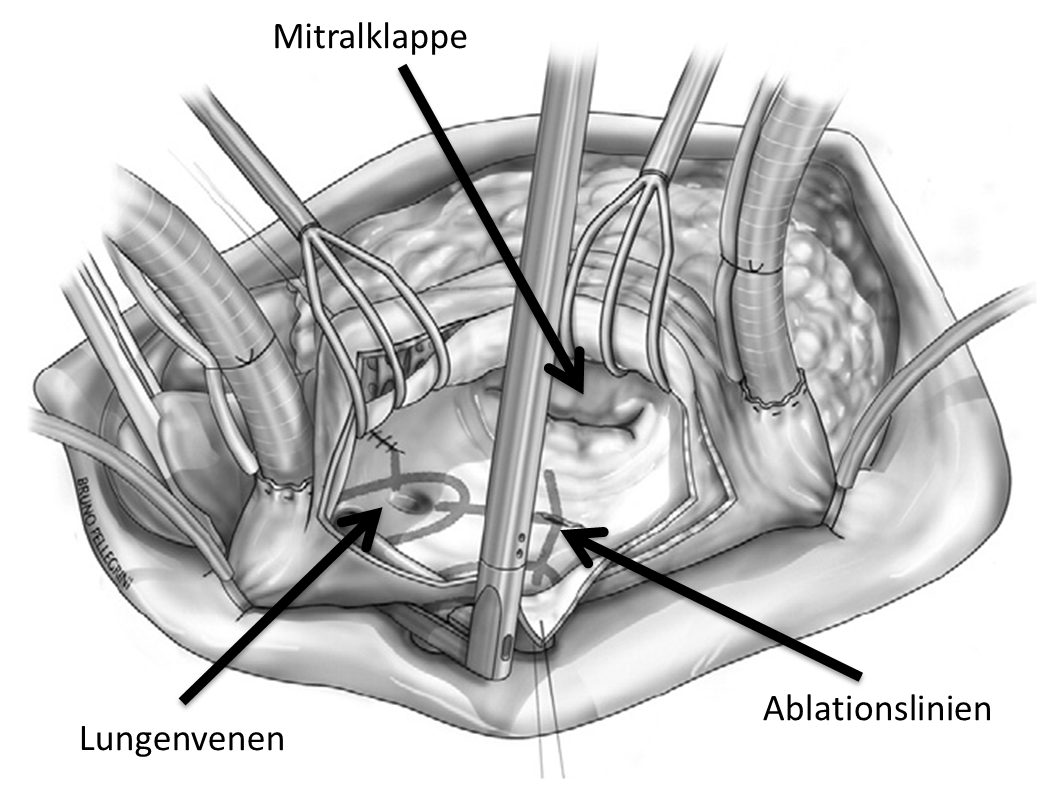

Atrial fibrillation can also be treated surgically in the open heart (“Cox-Maze procedure”). The atria are opened and closed again by means of incisions, which prevents the development and spread of atrial fibrillation. Today, a corresponding scar pattern can also be created using ablation forceps with radiofrequency energy or cold. Surgical ablation is mainly performed on patients with atrial fibrillation who are undergoing cardiac surgery. After unsuccessful catheter ablation, a mini-thoracotomy can be performed on the open atrium without opening the chest, even without an accompanying operation. This procedure is usually combined with closure of the left atrial appendage to reduce the risk of stroke. Careful selection of the right patients by an interdisciplinary Heart Team is also very important here.